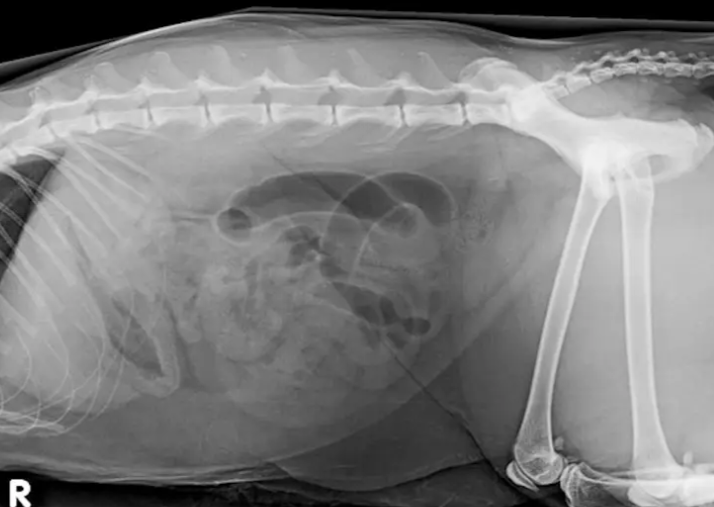

Ultrasound is a wonderful diagnostic tool in veterinary practice but is it always the most appropriate modality? Radiology has lost some of its glamour in recent years, overtaken by other modalities, yet it remains an essential tool in all aspects of veterinary practice. Its value must not be under estimated. This presentation will review multiple clinical scenarios where radiology trumps ultrasound and where radiology and ultrasound are complementary tests. There, of course, clinical situations where ultrasound is the most appropriate test for the patient. Using a system and case based approach, these choices will be explored with the aim of aiding the clinician choose the most appropriate imaging modality for the patients presenting complaint.